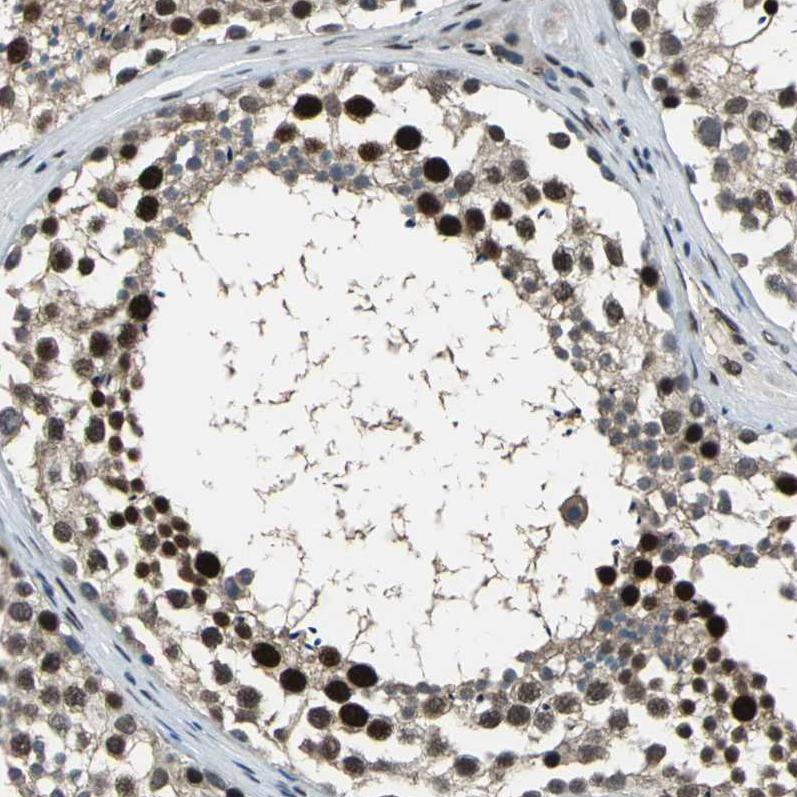

Immunohistochemical staining of human cerebral cortex, gastrointestinal, placenta and testis using Anti-ELF2 antibody HPA006057 (A) shows similar protein distribution across tissues to independent antibody HPA071166 (B).